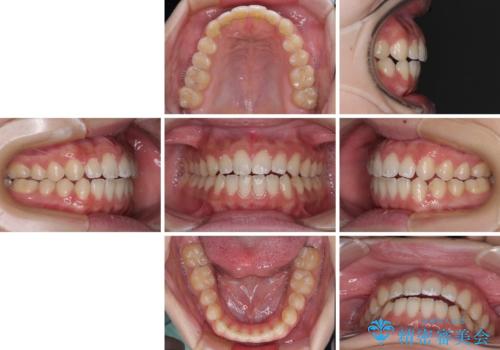

仕上がりとしては、もう少し上下前歯を接触させたかったのですが、ここまで改善されたことで患者様は大変満足され、治療を終えることとなりました。